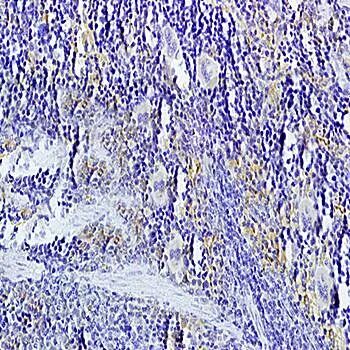

IHC-P of mouse liver tissue (Dilution at:1:200) using TNFSF14 antibody